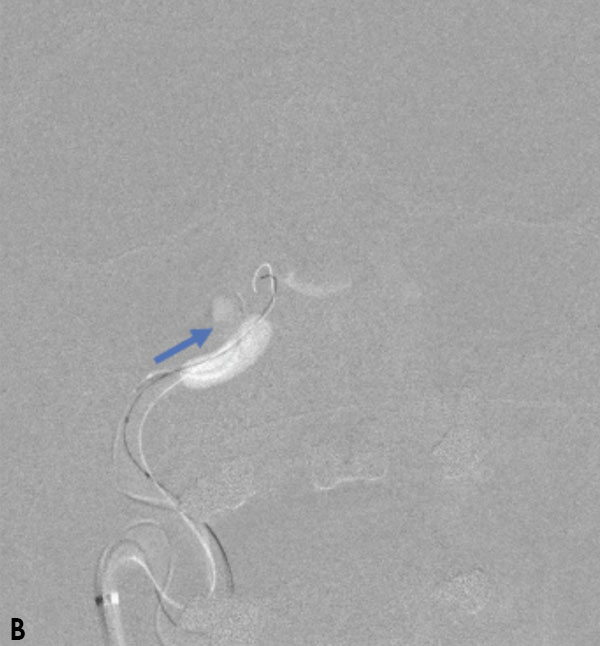

Collateral venous drainage into the orbit and skull base was observed (Figure A). After successful cannulation of the direct aperture between the right carotid artery and the cavernous sinus, balloon-assisted coil embolization of the posterolateral compartment was performed until the fistula was closed (Figure B and C). He experienced immediate cessation of his pulsatile tinnitus with an early improvement of the right VI nerve palsy and near-complete recovery of his vision within 6 weeks

Figure: (A) Right ICA Cavernous Fistula with Venous Shunting (B) Balloon Assisted Coil Embolization (C) Fistula Cured Post Embolization

A 59-year-old man who is otherwise healthy presented to his PCP with progressive right-sided pulsatile tinnitus for 4-6 weeks. His PCP and ENT evaluated him extensively and prescribed multiple courses of steroids and subsequent unremarkable MRI and MRA imaging. He developed acute onset diplopia secondary to a new partial right VI nerve palsy several days prior to our evaluation. A cerebral angiogram confirmed the presence of a high flow direct fistula of the right internal carotid artery–right cavernous sinus.